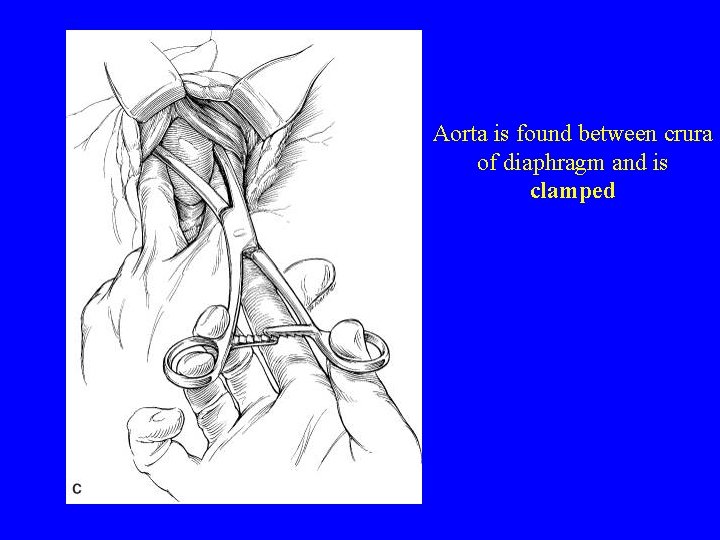

Aorta is found between crura of diaphragm and is clamped